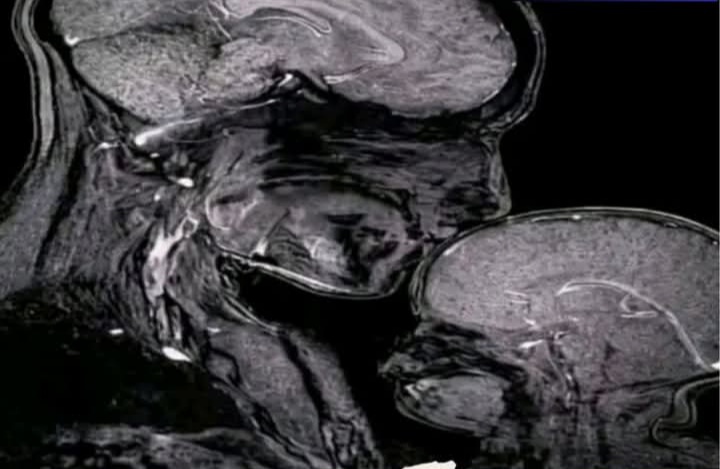

Selama ini, kita menganggap kasih sayang ibu adalah sesuatu yang bersifat “perasaan” saja. Namun, Rebecca Saxe, seorang pakar saraf dari MIT, berhasil memotret bukti fisik dari kasih sayang tersebut. Melalui teknologi MRI yang dimodifikasi, ia menangkap momen langka di mana ot4k seorang ibu dan bayinya bekerja dalam satu irama yang sama. Hal ini membuktikan bahwa sejak dini, tvbvh dan pikiran seorang anak memang sudah “terprogram” untuk terhubung dengan sang ibu.

Fenomena ini disebut dengan Sinkronisasi Saraf (Neural Synchrony). Bayangkan ot4k ibu dan bayi seperti dua instrumen musik yang berbeda namun memainkan lagu yang sama persis secara bersamaan. Ketika ibu menatap bayinya dengan penuh cinta atau memeluknya dengan hangat, ot4kk ibu melepaskan hormon oksitosin (hormon kebahagiaan). Uniknya, ot4k bayi akan menangkap sinyal ini dan melepaskan hormon yang sama, sehingga pola gelombang otak mereka menjadi selaras.